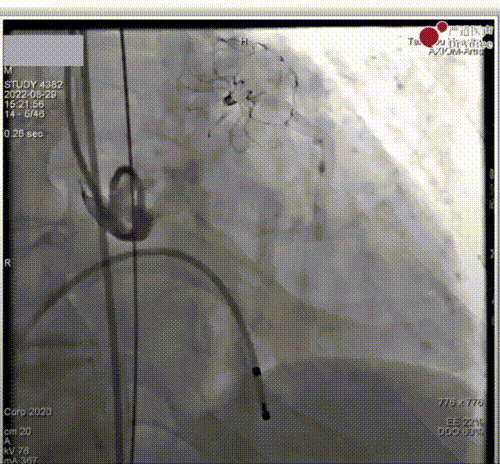

右窦中心位猪尾导管置于无冠窦底进行造影。可见Watchman封堵伞内皮化良好。

20 mm球囊预扩,右无粘连扩张不充分,无冠窦钙化完全推开,采用原计划TAV24瓣膜稍低位释放。

图7. 输送系统跨瓣

AV24瓣膜在瓣环下精准定位负位稳定释放。